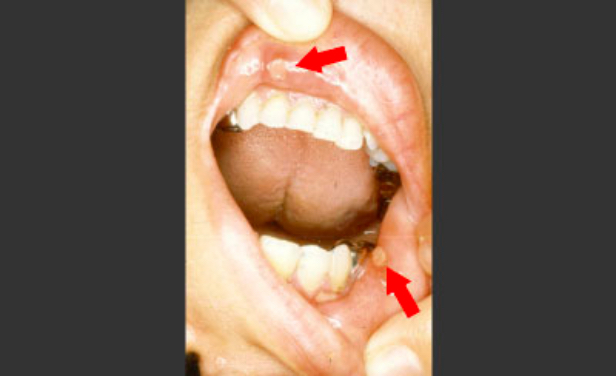

口内炎との違い、予防のコツ etc. いまこそ知りたい!口腔がん医療法人社団 ハートデンタルクリニック 歯科・矯正・審美・予防24時間Web予約可能な都城の歯医者です。

口内炎の種類と口腔がんとの見分け方 - 甲府市の歯医者なら、降矢歯科クリニック 歯科・矯正。

口内炎だと思っていたら口腔がんだった?患者数増加傾向の口腔がん。危険な口腔粘膜疾患は医師が解説ヨガジャーナルオンライン。